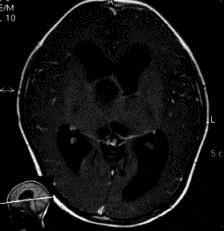

问题 病历摘要:??患者女性,6岁,半年来感觉视力模糊,近10天出现反复头痛,间有恶心呕吐,精神转差,查体:神志清楚,身高90cm,体重25Kg,血压90/55mmHg,右眼视力4.6,左眼视力4.8,双侧视乳头水肿,颈软,伸舌居中,四肢肌张力正常,肌力5级,双侧Babinski征(-)。 该患者就诊时,应作那些必要的检查?